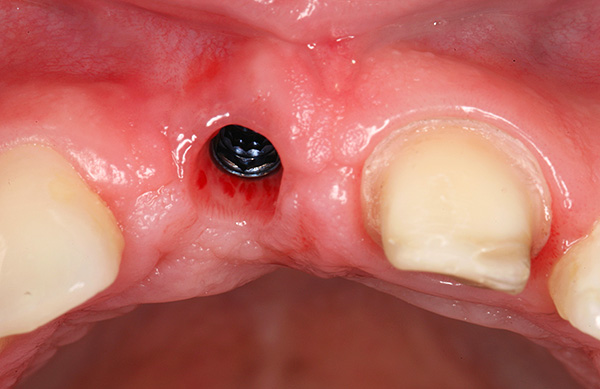

Talvez também seja importante mencionar a divergência de suturas, frequentemente aplicada à ferida após o implante. A foto abaixo mostra um exemplo do estado normal das suturas imediatamente após a cirurgia:

A divergência das suturas, como complicação, quase nunca é sinal de implantes dentários mal sucedidos, pois caracterizam mais o resultado do comportamento da própria pessoa. As violações podem ser muito diferentes: desde a não observância dos princípios de higiene bucal e ignorando as recomendações do médico, até o "toque" não autorizado na cavidade oral com dedos, palitos de dente, etc., o que leva a danos mecânicos nas suturas ou contribui para o início do processo inflamatório. Isso provoca a divergência de costuras no futuro.